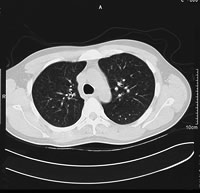

さらに詳しく調べるにはCTという検査が役立ちます。人間の体を「輪切り」にしたような画像を撮ります。以前は1枚撮るごとに息を止める必要がありましたが、最近のCTは数秒息が止められればすべての撮影がすむようになり、かかる時間がはるかに短くなりました。

さらにその肺をCTで見ると、正常の肺構造では一つひとつの肺胞は小さくて見えないため、全体に均一な灰 色に写ります(写真(3))が、肺胞が破れた肺は空気の部分が黒く写ります(写真(4))。黒く写った部分はまったく酸素の取り込みができないため、いく ら呼吸をしても酸素が血液の中に入ってこない状態となり、「息苦しさ」を感じるのです。

| (3)正常な肺のCT | (4)COPDの肺のCT |

| 【COPD】レントゲンでは、正常の人に比べて肺が膨張し、横隔膜をおし下げ、心臓も圧迫しているのがわかる。CTでは、正常の肺は均一な灰色で血管の白い点がみられるが、COPDでは肺が破壊され黒っぽくなり、血管が少なくなっている。 | |